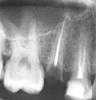

Amy Опубликовано 23 августа, 2011 Поделиться Опубликовано 23 августа, 2011 Уважаемые стоматологи!Возможно ли в данном случае поставить коронку на уцелевший корень? Ссылка на комментарий

pawa Опубликовано 23 августа, 2011 Поделиться Опубликовано 23 августа, 2011 (изменено) Нужно смотреть во рту, сколько там ещё кариеса осталось, но мало вероятно, что получится.если длина корня позволит сделать удлиннение наддесневой части, то можно. Изменено 23 августа, 2011 пользователем pawa Ссылка на комментарий

Doc Опубликовано 24 августа, 2011 Поделиться Опубликовано 24 августа, 2011 Уважаемые стоматологи!Возможно ли в данном случае поставить коронку на уцелевший корень? Теоретически можно, но гарантий никаких, а по стоимости получится больше, чем половина стоимости имплантата. В результате можно выбрать между двумя вариантами: Чуть дешевле и без всяких гарантий (с последующей переделкой на имплантат), либо подороже, но с пожизненной гарантией на имплантат и минимум лет десять на коронку. Зависит от Ваших финансовых возможностей и потребности сохранить зуб ЛЮБОЙ ценой. Окончательное решение за тем доктором, который будет изготавливать данную конструкцию, после осмотра зуба в полости рта. Ссылка на комментарий

Bier Опубликовано 25 августа, 2011 Поделиться Опубликовано 25 августа, 2011 удлинить наддесневую часть - имеете в виду ортодонтически тоже?есть 2 варианта1 - обрезать десну над зубом 2 - вытянуть зуб из десны. 2й способ на мой взгляд лучше, но более замороченный чем первый. Ссылка на комментарий

Doc Опубликовано 25 августа, 2011 Поделиться Опубликовано 25 августа, 2011 есть 2 варианта1 - обрезать десну над зубом 2 - вытянуть зуб из десны. 2й способ на мой взгляд лучше, но более замороченный чем первый. Зато более грамотный со всех сторон. Ссылка на комментарий